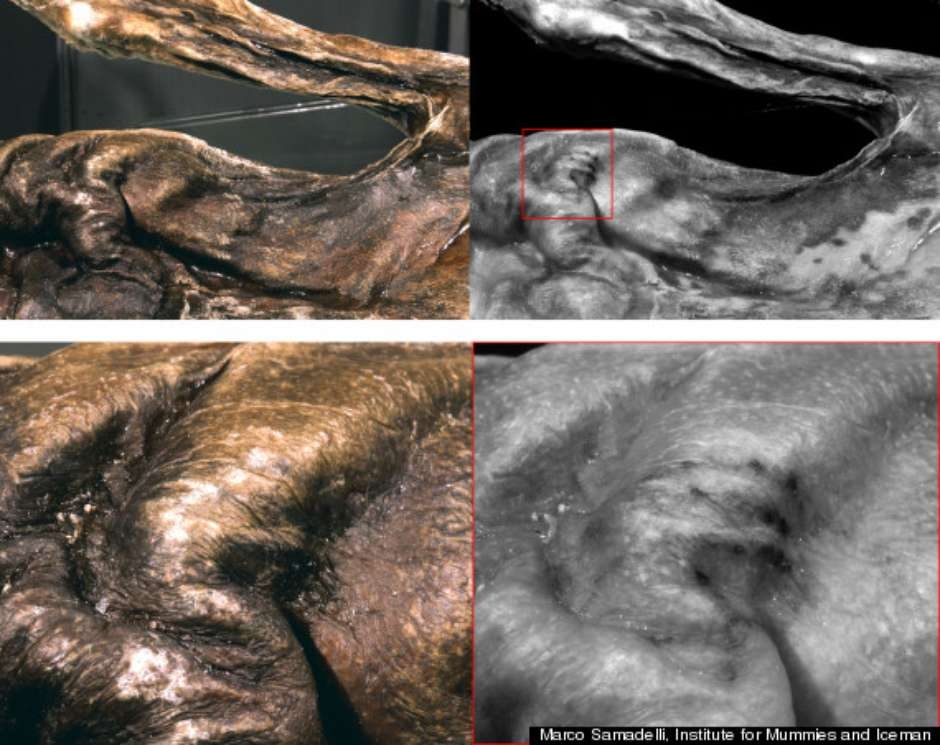

Tatuagem estranha é encontrada em múmia de “homem do gelo” A tatuagem é composta por quatro linhas paralelas que medem de 20 a 25 milímetros e estava na região do peito da múmia

Pesquisadores italianos anunciaram nesta segunda-feira que descobriram uma tatuagem “estranha” na múmia conhecida por “Ötzi the Iceman” (Ötzi, o Homem do Gelo, em tradução livre), que possui 5.300 anos. As informações são do The Huffington Post.A análise da pele da múmia revelou a tatuagem escondida em camadas profundas da pele de cor escura de Ötzi. Segundo informaram, a tatuagem é composta por quatro linhas paralelas que medem de 20 a 25 milímetros. Os pesquisadores acreditam que foram feitas por incisões na qual um carvão foi esfregado na pele.